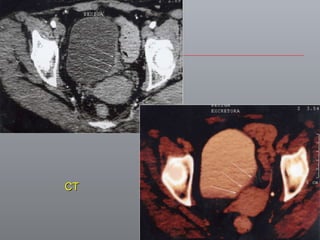

Câncer de Bexiga Estudos de imagens Diagnóstico Ultrassonografia Urografia excretora Estadiamento CT RNM Rx tórax  Cistoscopia + biópsia + biópsias randomizadas

CT

Câncer de BexigaEstudos de imagens Diagnóstico Ultrassonografia Urografia excretora Estadiamento CT RNM Rx tórax Cistoscopia + biópsia + biópsias randomizadas